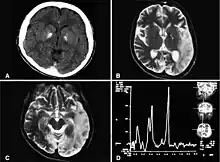

Basal ganglia calcification, cerebellar atrophy, increased lactate; a CT image of a person diagnosed with MELAS

MRI: Multifocal infarct-like cortical areas in different stages of ischemic evolution, areas that do not conform to any known vascular territory. Initial lesions often occur in the occipital or parietal lobes with eventual involvement of the cerebellum, cerebral cortex, basal ganglia, and thalamus.

Lactate levels are often elevated in serum and cerebrospinal fluid. MR spectroscopy may show an elevated lactate peak in affected and even unaffected brain areas. Muscle biopsy shows ragged red fibers. However, genetic evaluation should be done first, which eliminates the need for muscle biopsy in most cases. Diagnosis may be molecular or clinical: